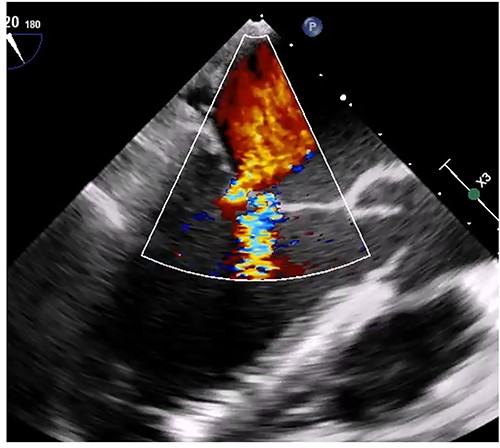

Median sternotomy was performed, and cardiopulmonary bypass was established via aortic and bicaval cannulation. Under cardiac arrest with antegrade cardioplegia perfusion, the LA was examined via the transseptal approach. The LA cavity was filled with the mass that the stalk was attached to the septal wall at the LA side, and the mass was too big and resected in pieces (Fig. 2). The mitral valve leaflet was intact, and the atrial septum was closed. Dilatated tricuspid annulus was fixed using a flexible band (Tailor Flexible band 29 mm, Abbott). After unclamping of the ascending aorta, a transesophageal echocardiogram points out moderate mitral regurgitation due to mitral annulus dilatation (Fig. 3). Cardiac arrest was performed again, and mitral annuloplasty was performed with a semi-rigid ring (Carpentier-Edwards Physio Ring II 26 mm, Edwards) via left atriotomy. His heart sinus rhythm returned to normal with successful weaning from cardiopulmonary bypass. After the transesophageal echocardiogram procedure, no evidence of the mass and residual mitral regurgitation was confirmed (Fig. 4).

Transesophageal echocardiogram after mitral annuloplasty. There was no residual mitral regurgitation.